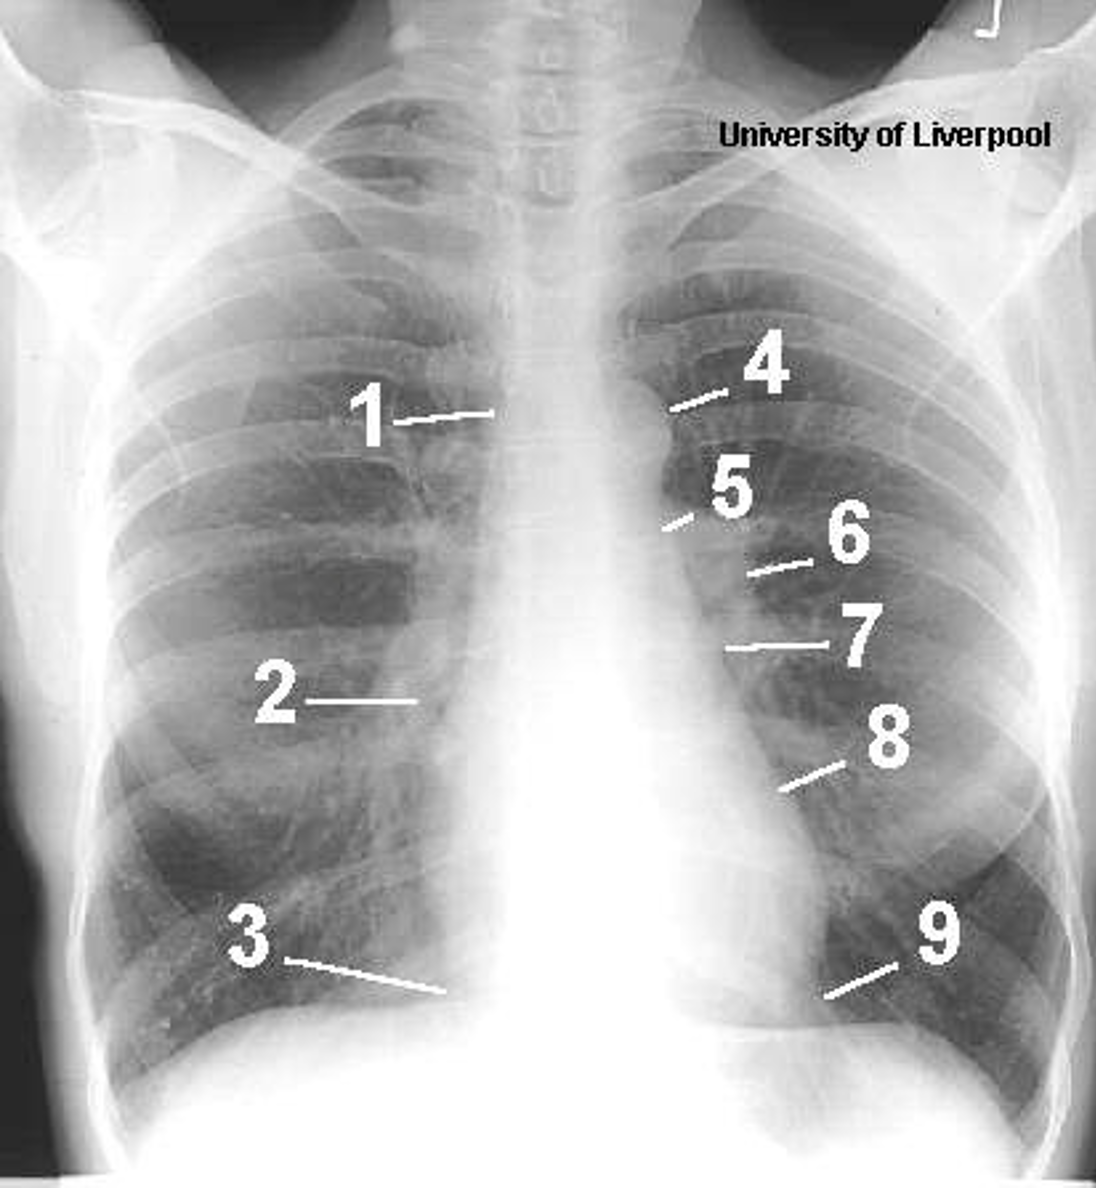

Name the mediastinal contours according to the numbers

1- superior vena cava

2- right atrium

3- inferior vena cava

4- aortic arch or knob

5- left pulmonary trunk

6- left pulmonary artery

7- left atrium

8- left ventricle

9- left cardiophrenic angle

Name the structures according to number